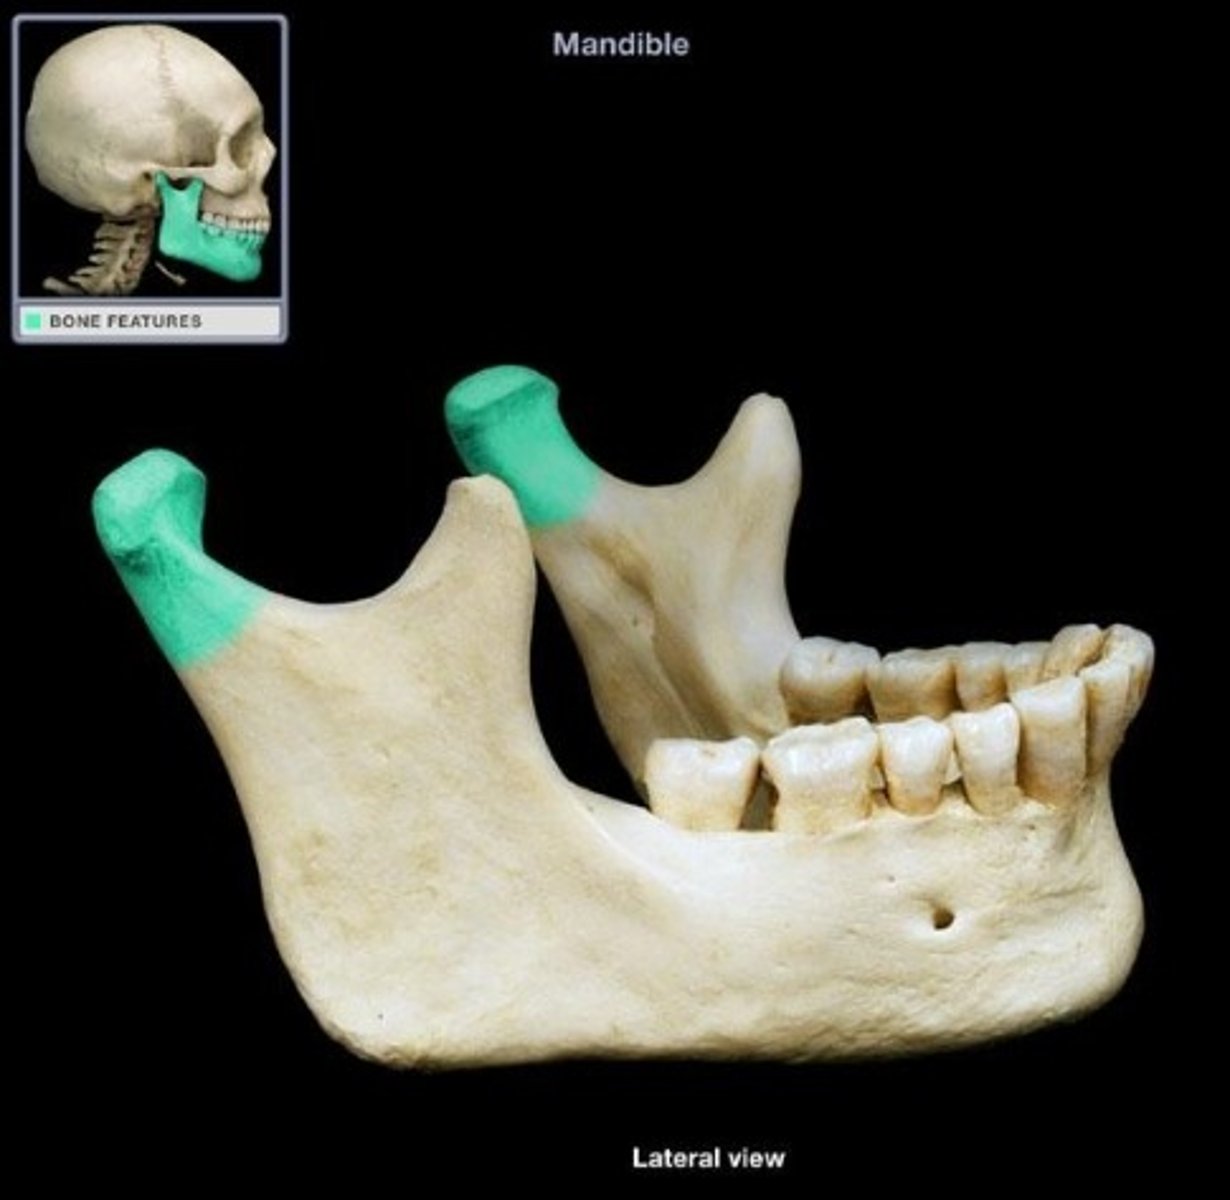

coronoid process ( anterior)

what is this

condyloid process ( posterior)

- makes up TMJ

At the gonion, also known as the angle of the mandible.

Where do the body and rami of the mandible meet?